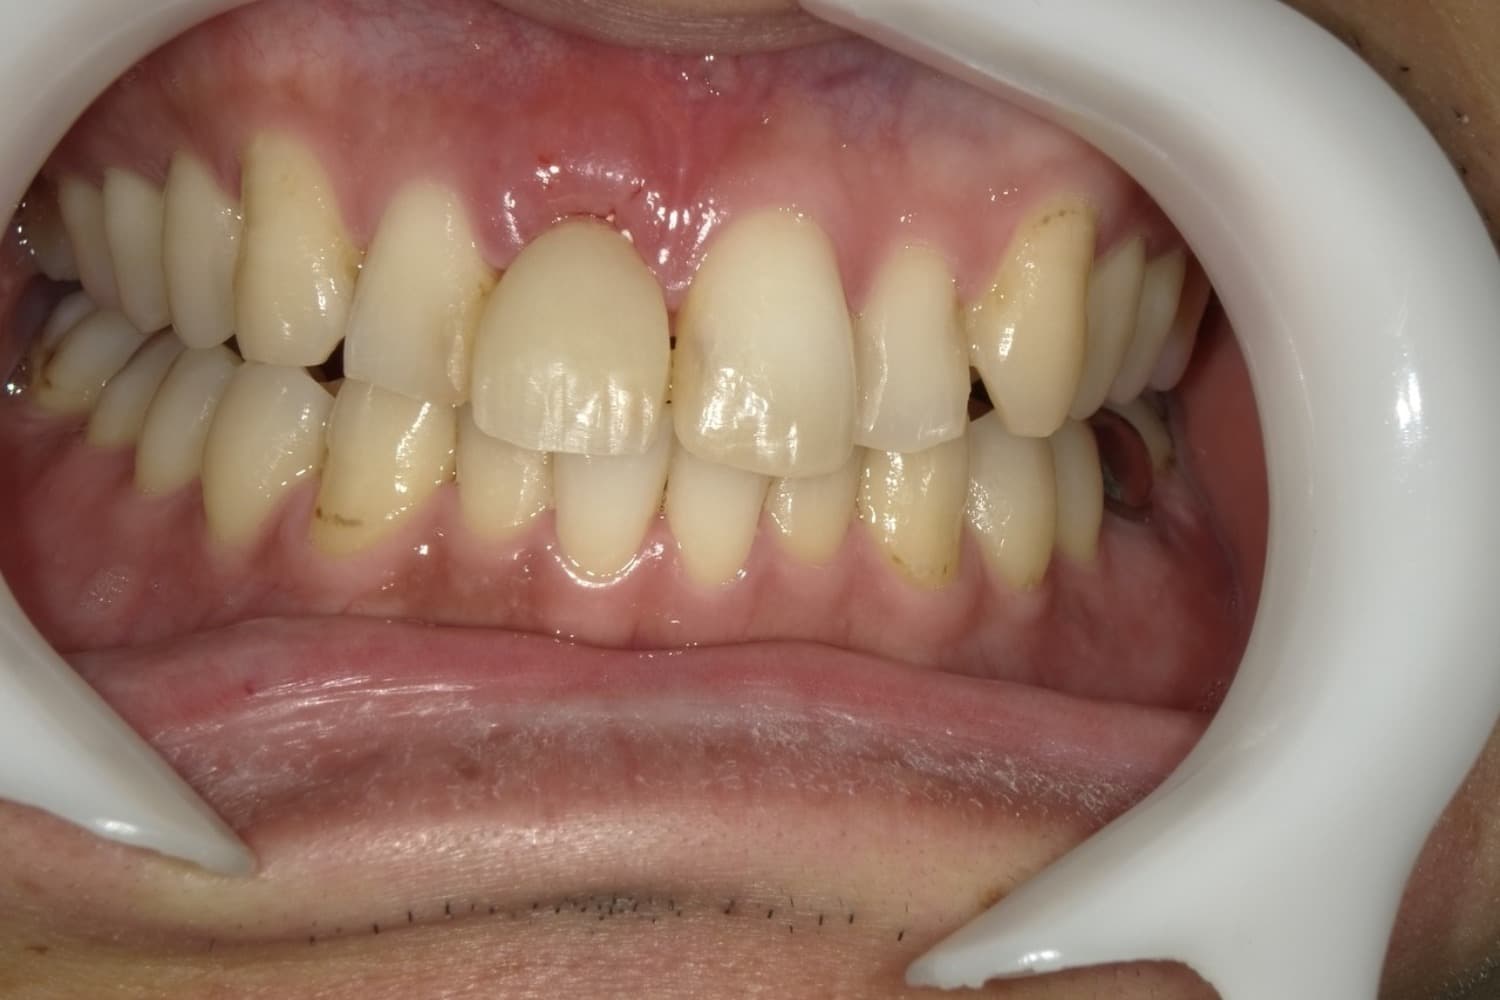

歯根破折した前歯のインプラント治療(30代男性)

Before

外傷によって歯根破折した前歯を抜歯してインプラント治療をおこなう(当日に仮歯の装着までおこなう)。

主訴

外傷によって歯根破折している。